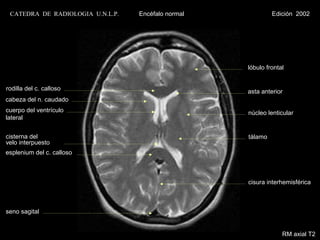

lóbulo frontal

rodilla del c. calloso                                 asta anterior

cabeza del n. caudado

cuerpo del ventrículo                                   núcleo lenticular

lateral

cisterna del                                            tálamo

velo interpuesto

esplenium del c. calloso

cisura interhemisférica

seno sagital

RM axial Densidad Protónica

CATEDRA DE RADIOLOGIA U.N.L.P.   Encéfalo normal            Edición 2002

RM axial T2